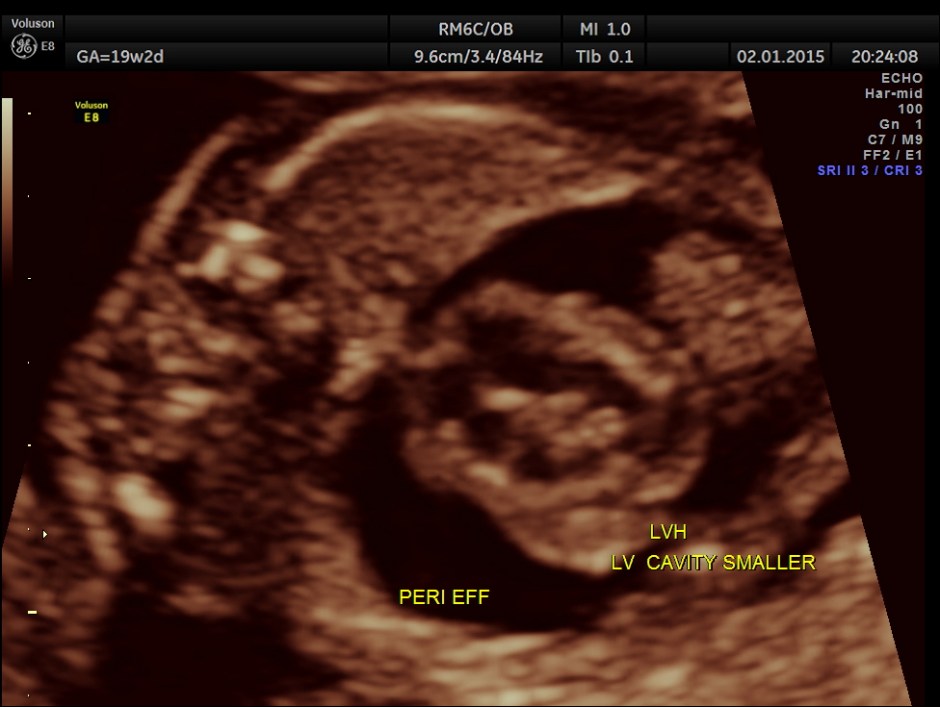

A large pericardial effusion is seen.

Apart from the VSD , left heart appears disproportionately smaller.

This fetus had a large pericardial effusion with structural defect of the heart – VSD and disproportionately smaller left heart – possibly co-arctation of aorta . The patient was advised chromosomal studies and was lost for follow up.